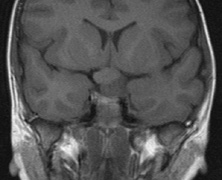

Intracranial leptomeningeal capillary vascular malformation (Figs. 21 and 22) is associated with seizures and contralateral neuromuscular weakness. Central nervous system involvement correlates highly with ipsilateral involvement of the V1 dermatome by a PWS.208,218

Fig. 21. Sturge-Weber syndrome: leptomeningeal vascular malformation.

Fig. 22. Axial T2-weighted (a) and coronal T1-weighted (b) images of a 16-year-old boy with a port-wine lesion over the right side of his face. The right hemisphere is markedly atrophic and abnormal draining veins are seen within the right lateral ventricle (arrowheads). (c, d) The entire right hemisphere is covered by an enhancing pial angioma and the choroid plexi are enlarged. Enhancing retinal angiomas (arrows), typical of Sturge-Weber syndrome, are seen in (d).

It has been hypothesized that the calcific changes reflect cellular anoxic injury secondary to venous stasis/poor drainage.219,220 Abnormal autonomic innervation has also been reported in association with the malformed cortical vessels—innervation only by noradrenergic fibers.221 Studies suggest that the normal increase in brain-blood flow to accommodate increased metabolic demand during seizure activity is blunted in affected brain regions of SWS.222 Thus, seizures in the setting of impaired perfusion may be exacerbating brain injury. Periods of contralateral weakness (days to weeks) can follow a prolonged seizure episode.206,223